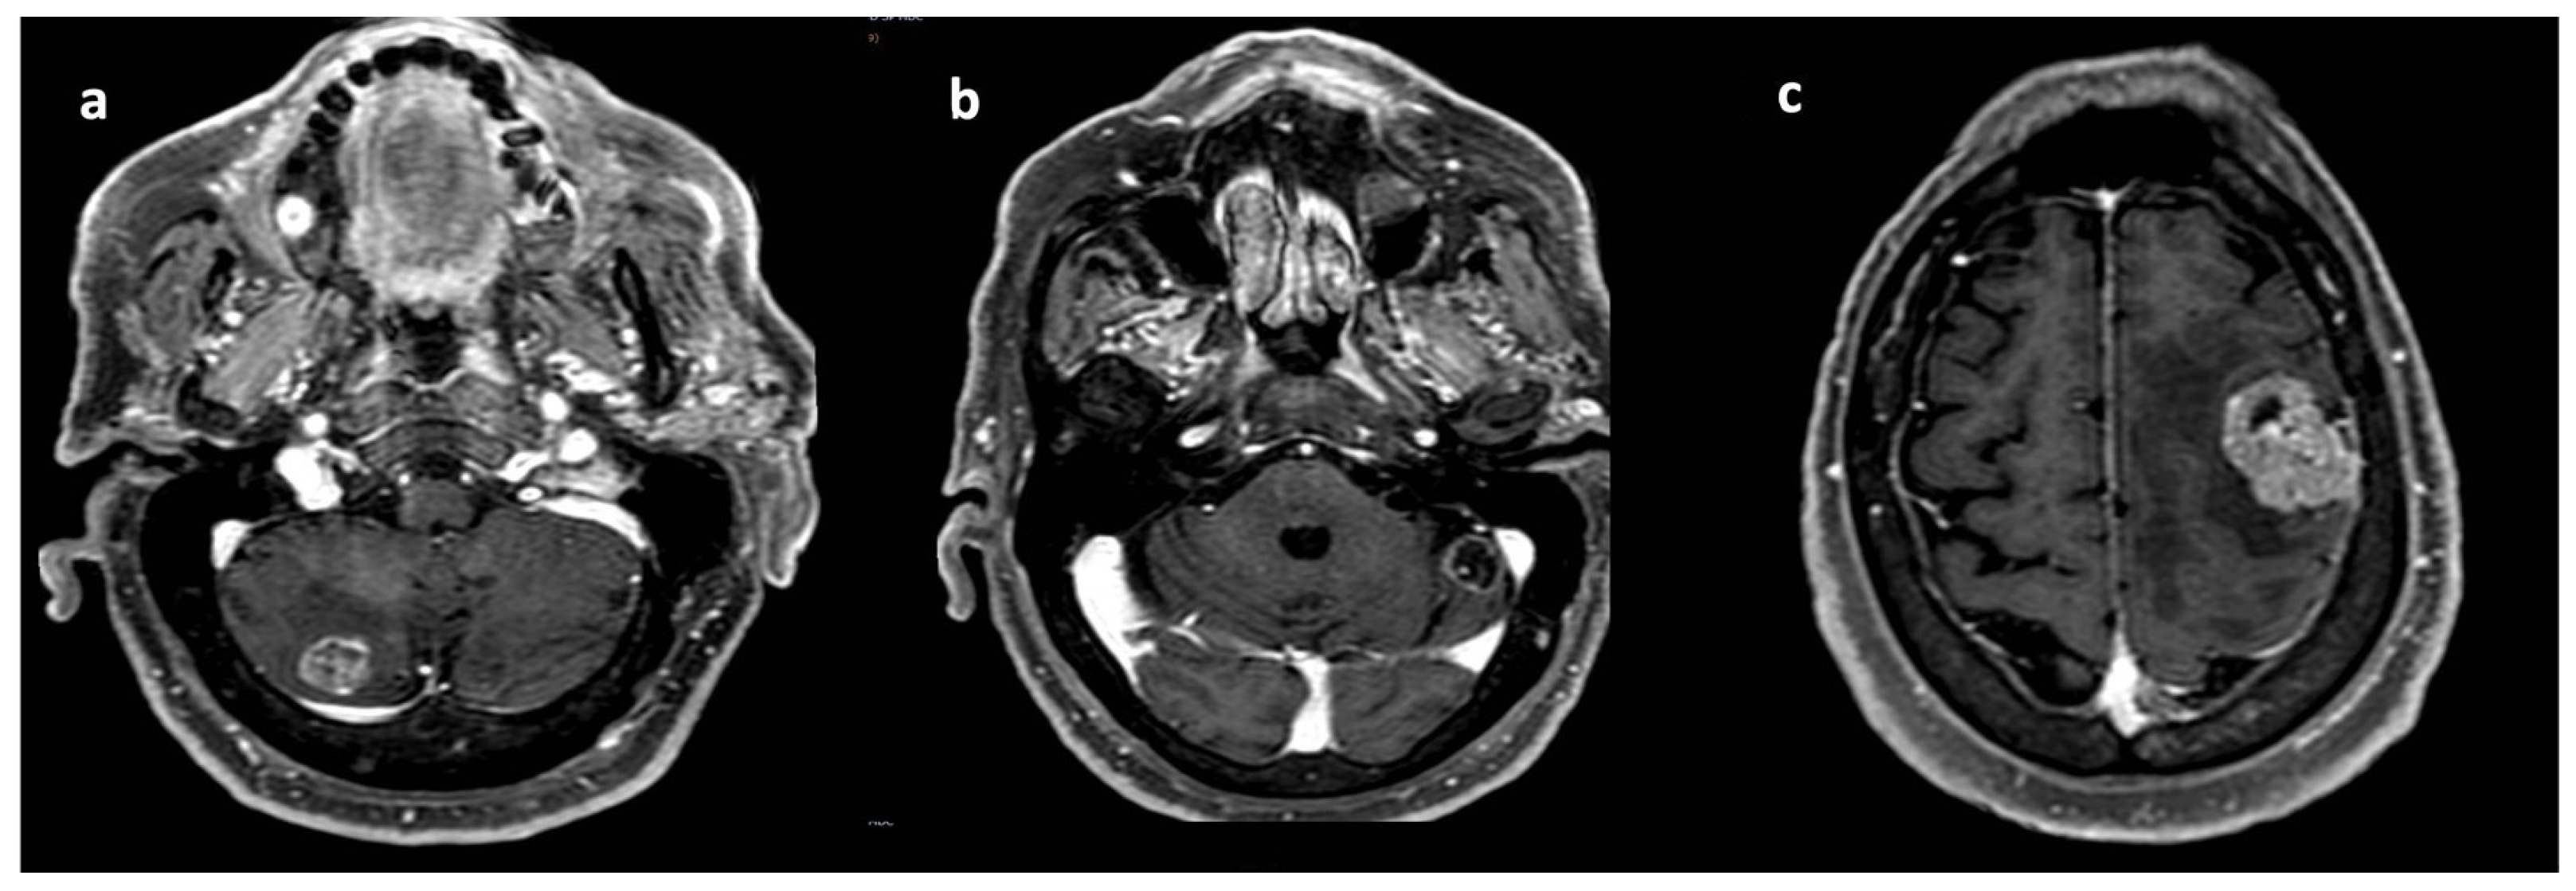

2. Case Report